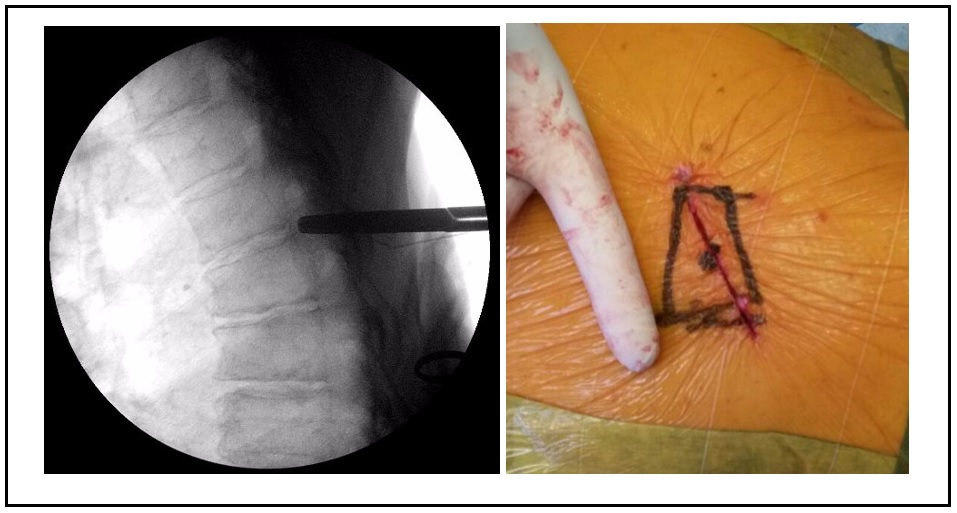

Existen múltiples técnicas para la descompresión medular en la columna torácica, cada una con sus ventajas y desventajas y con distintos requerimientos de destrezas quirúrgicas. Se han desarrollado técnicas mínimamente invasivas que disminuyen las tasas de morbilidad, con buenos resultados funcionales. Se presenta el caso de un hombre de 64 años, con clínica de compresión medular, una hernia de disco central, calcificada a nivel del quinto disco torácico, migrada hasta el borde inferior de la sexta vértebra torácica, con franca compresión medular. Se realizó un abordaje lateral transpleural mínimamente invasivo, con una corpectomía parcial posterior de la sexta vértebra, sin fijación adicional. El paciente tuvo una buena evolución, sin progresión del cuadro neurológico ni dolor costal residual. Los abordajes laterales mínimamente invasivos son técnicas válidas para tratar patologías compresivas de la columna torácica, con bajas tasas de morbimortalidad y una rápida recuperación. Abstract There are multiple techniques for spinal cord decompression in the thoracic spine, each with its advantages and disadvantages, and requiring different surgical skills. Recently, minimally invasive techniques have been developed, reducing morbidity rates and achieving good functional results. We present the case of a 64-year-old male with spinal compression symptoms, central disc herniation calcified at the fifth thoracic vertebra, which migrated to the lower end of the sixth thoracic vertebra. Diagnosis was clear for spinal cord compression. Partial posterior corpectomy of the sixth vertebra was performed with a minimally invasive transthoracic transpleural lateral approach and without additional fixation. The patient had a good outcome on follow-up, without progression of neurological symptoms or residual rib pain. Minimally invasive lateral approaches are valid techniques for the treatment of compression disorders of the thoracic spine, with low rates of morbidity and mortality, and a rapid recovery.Descargas